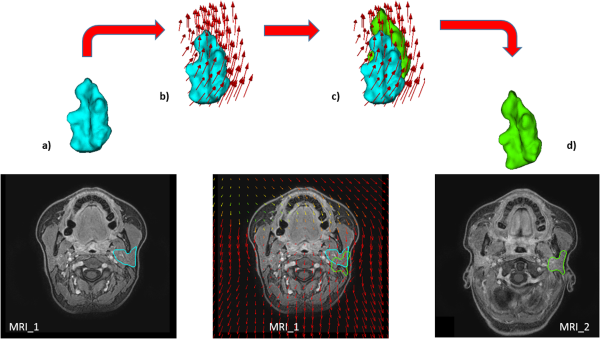

The second approach (named DIR_Mesh) was an optimized homemade version of the Transformix function, based on mesh deformation. This method was previously proposed and evaluated, , and it applied the deformation field (estimated using MRI_1 as fixed image and MRI_2 as moving image) to the vertices of a 3D mesh generated from the binary segmentation of PGs on MRI_1. These meshes were constructed using a wavelet-based surface reconstruction method, where, starting from manual cross-sectional contours, image voxel segmentation processing was combined with implicit surface streaming methods using wavelets. This method was proved to generate smoothed and regular surfaces, with a mesh quality comparable or even better than other state-of-art methods. Once the mesh was deformed, it was cut on the corresponding planes of MRI_2 to obtain the propagated binary masks on each slice (see Figure 1). The method was implemented based on the open-source software packages Insight Segmentation and Registration Toolkit (www.itk.org) and Visualization Toolkit (www.vtk.org).

Figure 1

Schematic description of the DIR_Mesh contour propagation algorithm. From the delineated contour on MRI_1, a mesh was generated (A); the estimated vector field was applied to it (B) in order to deform the vertices of the mesh (C); the obtained deformed mesh (D) was finally cut on the correspondent slice on MRI_2.